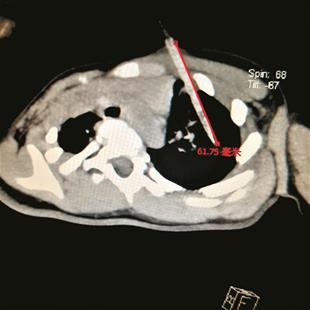

120赶到后,紧急抢救了十多分钟,没有效果。随后彭老师被送到孝昌县第一人民医院继续抢救,5时40分左右,医生向其妻宣布抢救无效。